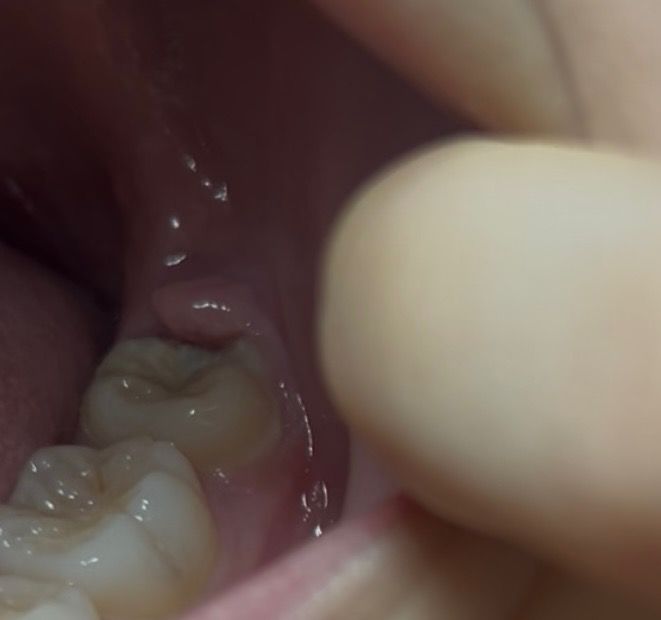

잇몸 거슬림 부음 약간의 통증 사랑니인가요?

며칠전부터 제일 안쪽 잇몸들 붓기 시작하더니

이게 어금니가자라면서 잇몸이 붓고 통증이오는건지

아니면 사랑니의신호인지 ㅜ 궁금합니다

• 2번 째 사진

사진에 보이는건 사랑니는 아닌거 같고 가장 뒤 어금니 맹출이 다안됫거나 잇몸이 과증식된 상태 같습니다.

네 잇몸안에 파묻힌 사랑니가 치관주위염을 유발해 잇몸이 붓고, 아픈 것 같습니다 사랑니 발치 상담 받아보세요